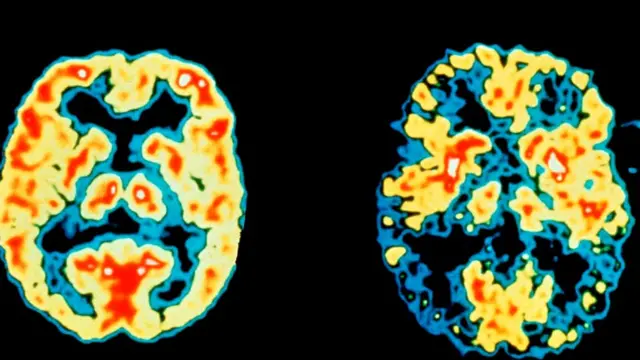

Как показали исследования на животных, сон способствует освобождению мозга от отходов его жизнедеятельности, таких как амилоид.

Автор фото, SPL

Скопление амилоидных бляшек считается одним из классических признаков болезни Альцгеймера. Эта недавно выявленная функция сна - "промывание мозгов" для устранения токсичных продуктов - вызывает большой интерес ученых.